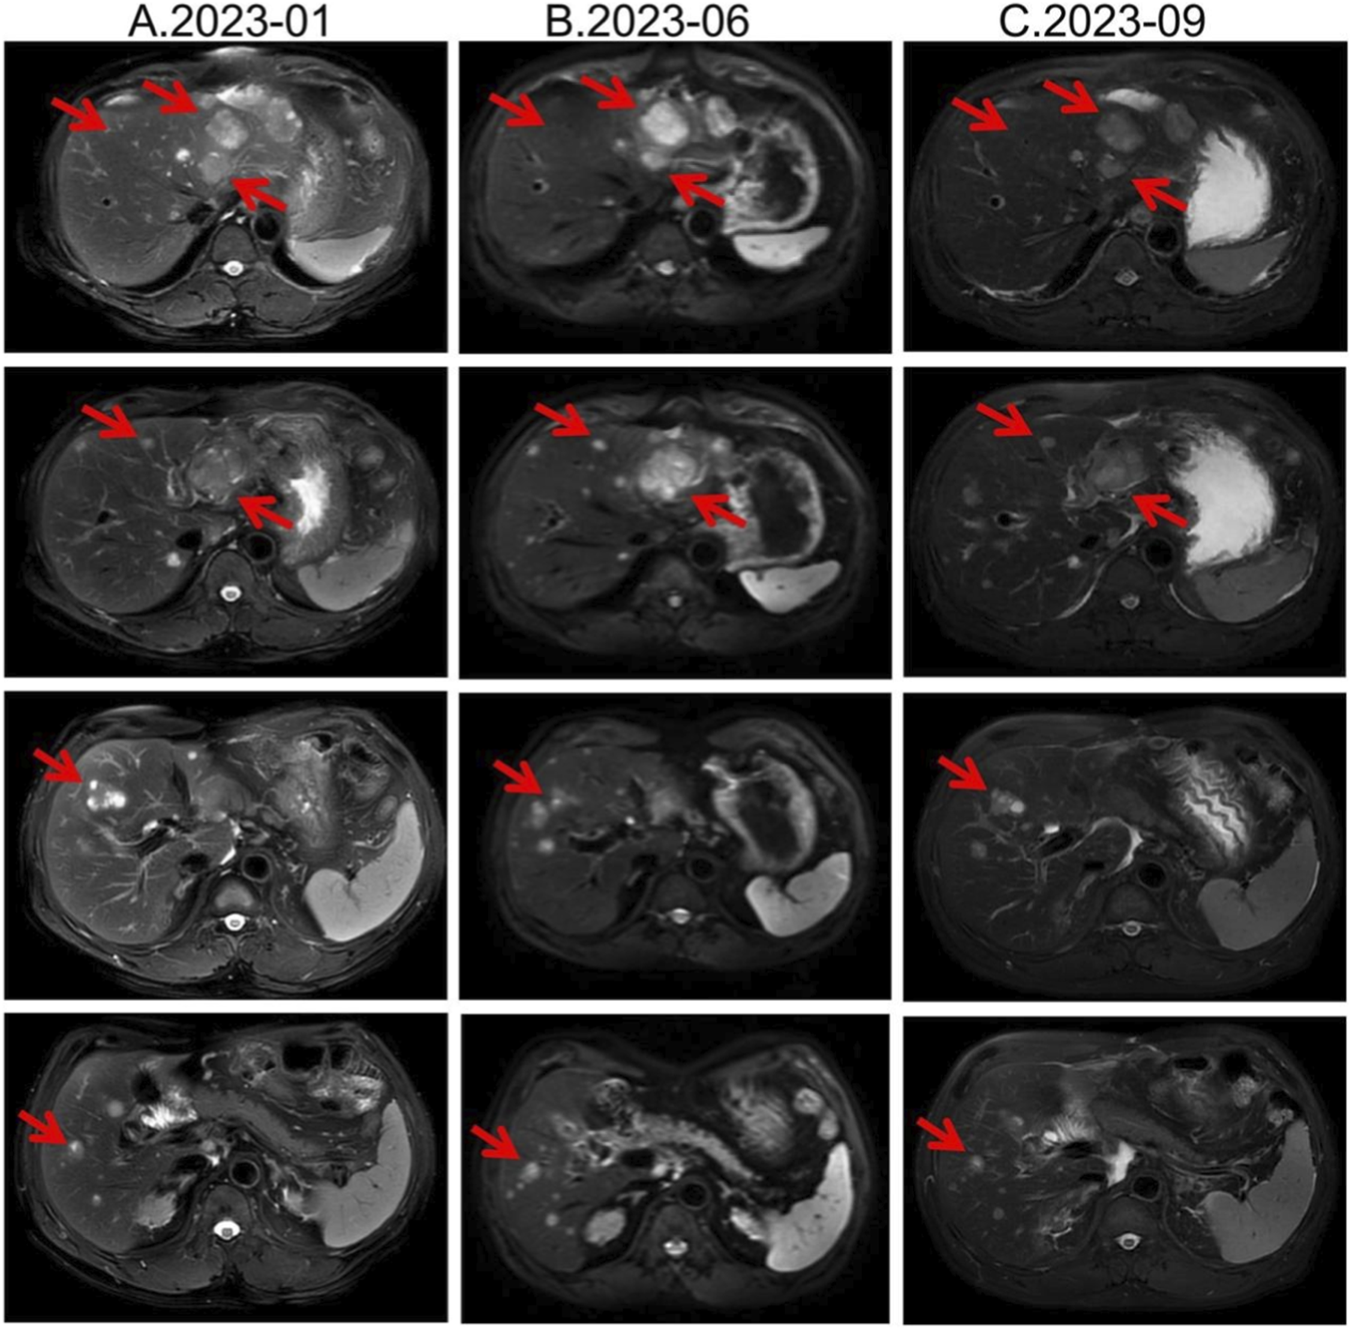

Second-line therapy began in September 2022, with surufatinib 300 mg daily. In the SANET III phase III trial, surufatinib significantly prolonged PFS in pNETs (Xu et al., 2020). The MRI efficacy evaluations in January, June, and September 2023 all demonstrated SD (Figure 2). During treatment he developed mild-to-moderate proteinuria and anemia (hemoglobin 78 g/L). Considering the patient experienced intermittent melena in September 2023, after MDT discussion and temporary drug discontinuations he was screened for the “[177Lu]Lu-DOTATATE Injection versus Long-Acting Octreotide Study”. [68Ga]Ga-DOTATATE imaging demonstrated that some hepatic metastases were SSTR-negative, and he therefore failed screening (Figure 3). Surufatinib was resumed at a reduced dose of 200 mg daily. On 8 January 2024, the patient passed approximately 200 mL of dark red stool. A gastroscopy revealed multiple small-intestinal ulcers at the gastroenteric anastomosis site (A1 stage, Forrest III). After a comprehensive evaluation of efficacy and safety, surufatinib was discontinued.

FIGURE 2

Lesion changes in patients treated with second-line surufatinib. (A) 2023-01 MRI: Multiple enhanced nodular shadows in the liver, with the larger ones located in the left lateral lobe of the liver, approximately 4.4 cm × 3.5 cm in size. Treatment response evaluation: SD. (B) 2023-06 MRI: Multiple enhanced nodules in the liver, with the larger ones located in the left lateral lobe of the liver. Treatment response evaluation: SD. (C) 2023-09 MRI: Multiple enhanced nodules in the liver, with the larger ones located in the left lateral lobe of the liver. Treatment response evaluation: SD.